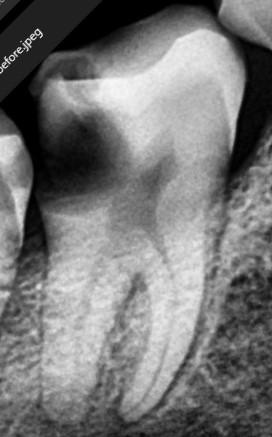

Before

Lower Molar

Severe Infection

Lower Molar Root Canal

Infection in the lower molar causing intense pain and swelling. Root canal treatment was performed to save the tooth.

Severe infection eliminated

Pain relief within 24 hours

Natural tooth saved